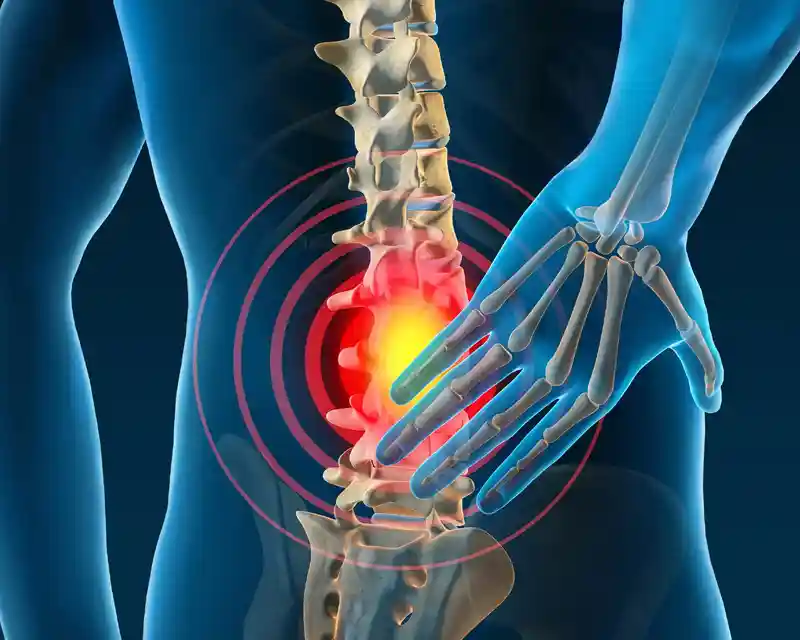

Sciatica is a painful condition caused by compression or irritation of the sciatic nerve, which runs from the lower back through the hips and down each leg. It often results in pain, numbness, or a burning sensation in the lower back, buttocks, and legs.

According to Ayurveda, sciatica arises due to an imbalance of the Vata dosha, leading to nerve irritation and muscular tension. Dr. Padmasiri Udugama’s Ayurvedic treatments focus on reducing inflammation, easing nerve compression, and restoring natural balance through herbal medicines, medicated oil therapies, and traditional massage techniques. These treatments help relieve pain and improve mobility, offering long-lasting comfort and recovery.